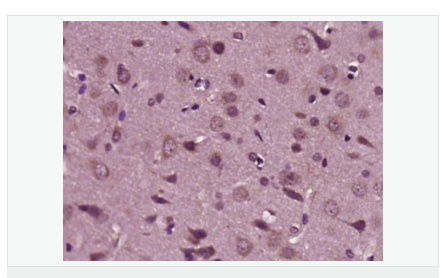

| 產品應用 | WB=1:500-2000 ELISA=1:5000-10000 IHC-P=1:100-500 IHC-F=1:100-500 ICC=1:100-500 IF=1:200-800 (石蠟切片需做抗原修復) not yet tested in other applications. optimal dilutions/concentrations should be determined by the end user. |

| 產品介紹 | The protein encoded by this gene is a membrane glycoprotein that that mediates cell-cell signaling and plays a critical role in the growth and development of multiple organ systems. An extraordinary variety of different isoforms are produced from this gene through alternative promoter usage and splicing. These isoforms are expressed in a tissue-specific manner and differ significantly in their structure, and are classified as types I, II, III, IV, V and VI. Dysregulation of this gene has been linked to diseases such as cancer, schizophrenia, and bipolar disorder (BPD). [provided by RefSeq, Jun 2014] Function: Direct ligand for ERBB3 and ERBB4 tyrosine kinase receptors. Concomitantly recruits ERBB1 and ERBB2 coreceptors, resulting in ligand-stimulated tyrosine phosphorylation and activation of the ERBB receptors. The multiple isoforms perform diverse functions such as inducing growth and differentiation of epithelial, glial, neuronal, and skeletal muscle cells; inducing expression of acetylcholine receptor in synaptic vesicles during the formation of the neuromuscular junction; stimulating lobuloalveolar budding and milk production in the mammary gland and inducing differentiation of mammary tumor cells; stimulating Schwann cell proliferation; implication in the development of the myocardium such as trabeculation of the developing heart. Isoform 10 may play a role in motor and sensory neuron development. Subunit: The cytoplasmic domain interacts with the LIM domain region of LIMK1. Interacts with ERBB3 and ERBB4. Subcellular Location: Pro-neuregulin-1, membrane-bound isoform: Cell membrane; Single-pass type I membrane protein. Neuregulin-1: Secreted. Isoform 8: Nucleus. Isoform 9: Secreted. Isoform 10: Membrane; Single-pass type I membrane protein. Tissue Specificity: Type I isoforms are the predominant forms expressed in the endocardium. Isoform alpha is expressed in breast, ovary, testis, prostate, heart, skeletal muscle, lung, placenta liver, kidney, salivary gland, small intestine and brain, but not in uterus, stomach, pancreas, and spleen. Isoform 3 is the predominant form in mesenchymal cells and in non-neuronal organs, whereas isoform 6 is the major neuronal form. Isoform 8 is expressed in spinal cord and brain. Isoform 9 is the major form in skeletal muscle cells; in the nervous system it is expressed in spinal cord and brain. Also detected in adult heart, placenta, lung, liver, kidney, and pancreas. Isoform 10 is expressed in nervous system: spinal cord motor neurons, dorsal root ganglion neurons, and brain. Predominant isoform expressed in sensory and motor neurons. Not detected in adult heart, placenta, lung, liver, skeletal muscle, kidney, and pancreas. Not expressed in fetal lung, liver and kidney. Type IV isoforms are brain-specific. Post-translational modifications: Proteolytic cleavage close to the plasma membrane on the external face leads to the release of the soluble growth factor form. N- and O-glycosylated. Extensive glycosylation precedes the proteolytic cleavage. DISEASE: Note=A chromosomal aberration involving NRG1 produces gamma-heregulin. Translocation t(8;11) with ODZ4. The translocation fuses the 5'-end of ODZ4 to NRG1 (isoform 8). The product of this translocation was first thought to be an alternatively spliced isoform. Gamma-heregulin is a soluble activating ligand for the ERBB2-ERBB3 receptor complex and acts as an autocrine growth factor in a specific breast cancer cell line (MDA-MB-175). Not detected in breast carcinoma samples, including ductal, lobular, medullary, and mucinous histological types, neither in other breast cancer cell lines. Similarity: Belongs to the neuregulin family. Contains 1 EGF-like domain. Contains 1 Ig-like C2-type (immunoglobulin-like) domain. SWISS: Q02297 Gene ID: 3084 Database links: Entrez Gene: 3084 Human Entrez Gene: 211323 Mouse Omim: 142445 Human SwissProt: Q02297 Human Unigene: 453951 Human Unigene: 668810 Human Unigene: 153432 Mouse Important Note: This product as supplied is intended for research use only, not for use in human, therapeutic or diagnostic applications. 神經膠質生長因子 |